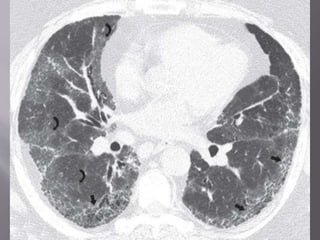

 Typical HRCT findings- GGO , irregular linear

opacity ( reticulations ), traction bronchietasis.

 GGO found in patients , changed into reticular

opacity after few years.

 Honeycombing, if present, tends to be mild

 Lower lobe predominance is common. Upper

lobe is uncommon in NSIP and should suggest

another diagnosis (chronic HP, sarcoidosis)

 Characteristic finding of NSIP is relative

sparing of the immediate subpleural lung in

dorsal region of lower lobe.

 CT findings tend to improve with treatment in

pts who mainly have GGO predominance (cellular;

airspace) than pts who have predominant fibrosis

on previous scans.